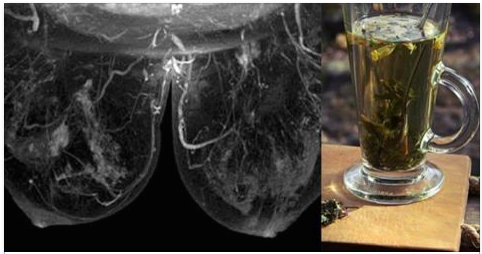

Народне лікування мастопатії

Народна медицина також має в своєму розпорядженні ефективними засобами для відновлення жіночого здоров'я. Добре зарекомендував себе чай на основі валеріани та звіробою.

СКЛАДОВІ

- 1 ч. Л. подрібненого кореня валеріани

- 2 ч. Л. звіробою

- 1 ч. Л. листя м'яти

- 0,5 ч. Л. квіток ромашки

- 1 ч. Л. насіння фенхелю

- 1 ч. Л. насіння кмину